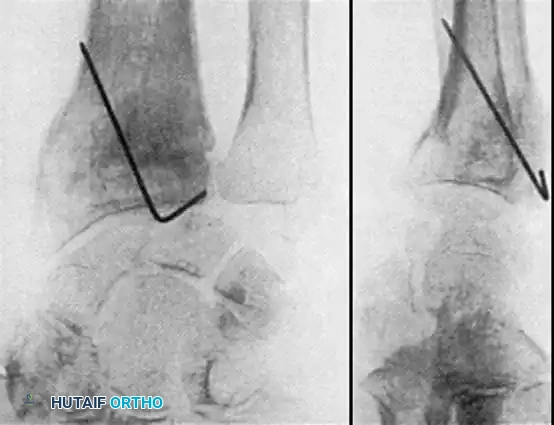

Type II distal radial shear fractures (Barton type) usually require ORIF. These fractures are almost impossible to treat by closed means. Buttress plate fixation of volar Barton fractures is the gold standard.

Type III compression injuries require operative treatment if intraarticular damage is significant or radial shortening is severe. Careful restoration of the articular surface, radial angulation, and length is crucial. Fixation with multiple K-wires or plates is often necessary, and cancellous bone grafting is frequently required to fill impacted metaphyseal voids.

Often, a combination of open and closed techniques is necessary to treat Type III fractures satisfactorily.

Fig. 54-103 A and B, Four-part type III distal radial fracture treated by open reduction, internal fi xation of intraarticular component, iliac bone grafting, and external fi xation. C and D, Follow-up radiographs at 5 weeks (C) and 3 years (D) show anatomical restoration of joint surface, maintenance of radial length, and absence of degenerative changes. (From Fernandez DL: Fractures of the distal radius: operative treatment, Instr Course Lect 42:73, 1993.)

Fig. 54-103 A and B, Four-part type III distal radial fracture treated by open reduction, internal fixation of intraarticular component, iliac bone grafting, and external fixation. C and D, Follow-up radiographs at 5 weeks (C) and 3 years (D) show anatomical restoration of joint surface, maintenance of radial length, and absence of degenerative changes.